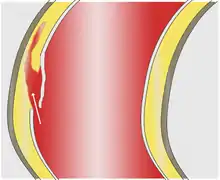

Quando a área deformada do vaso toma forma esférica, dá-se o nome de aneurisma saciforme ou sacular (de saco), ou quando tem forma alongada através do eixo principal do vaso, aneurisma fusiforme (de fuso).

O aneurisma sacular se desenvolve na parede de artérias com defeitos congênitos decorrente do aumento do fluxo sanguíneo ou pressão arterial, entre outras causas. É comum esses aneurismas se romperem, provocando hemorragia cerebral, causando até um acidente vascular encefálico hemorrágico (mais conhecido como derrame cerebral). É bastante perigoso e acarreta hemorragia com frequência.